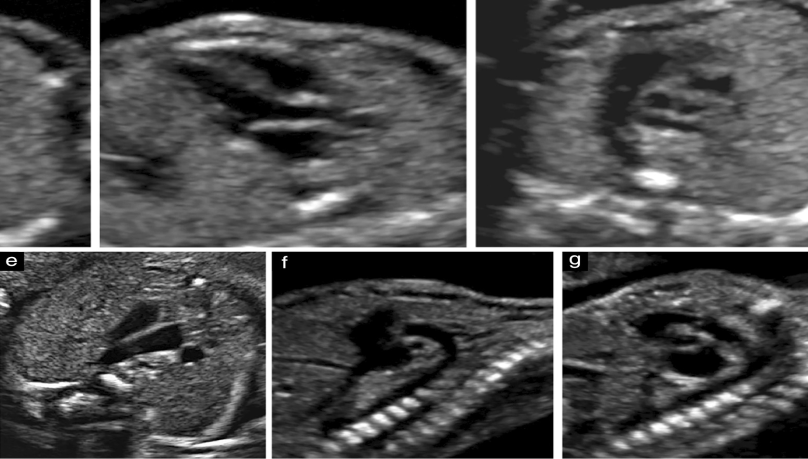

Anomaly in the context of medical imaging, particularly during pregnancy, usually refers to congenital anomalies or birth defects. Fetal echocardiography, on the other hand, is a specialized type of ultrasound that specifically focuses on imaging the heart of the developing fetus.